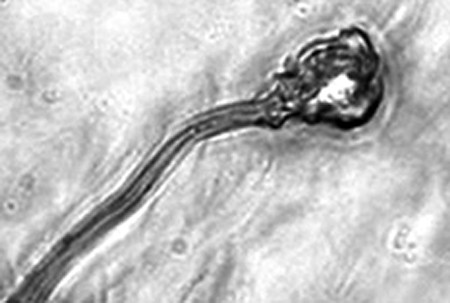

據(jù)報(bào)告的主要作者卡里姆教授介紹,這種試管培育精子(IVDsperm)與人類(lèi)自然產(chǎn)生的精子并不完全一樣,但兩者擁有4個(gè)重要的相似點(diǎn):它們包含有23個(gè)染色體;有精子那樣的頭和尾巴;有可以使卵細(xì)胞受精的蛋白質(zhì);它們也可以像天然精子一樣游動(dòng)。